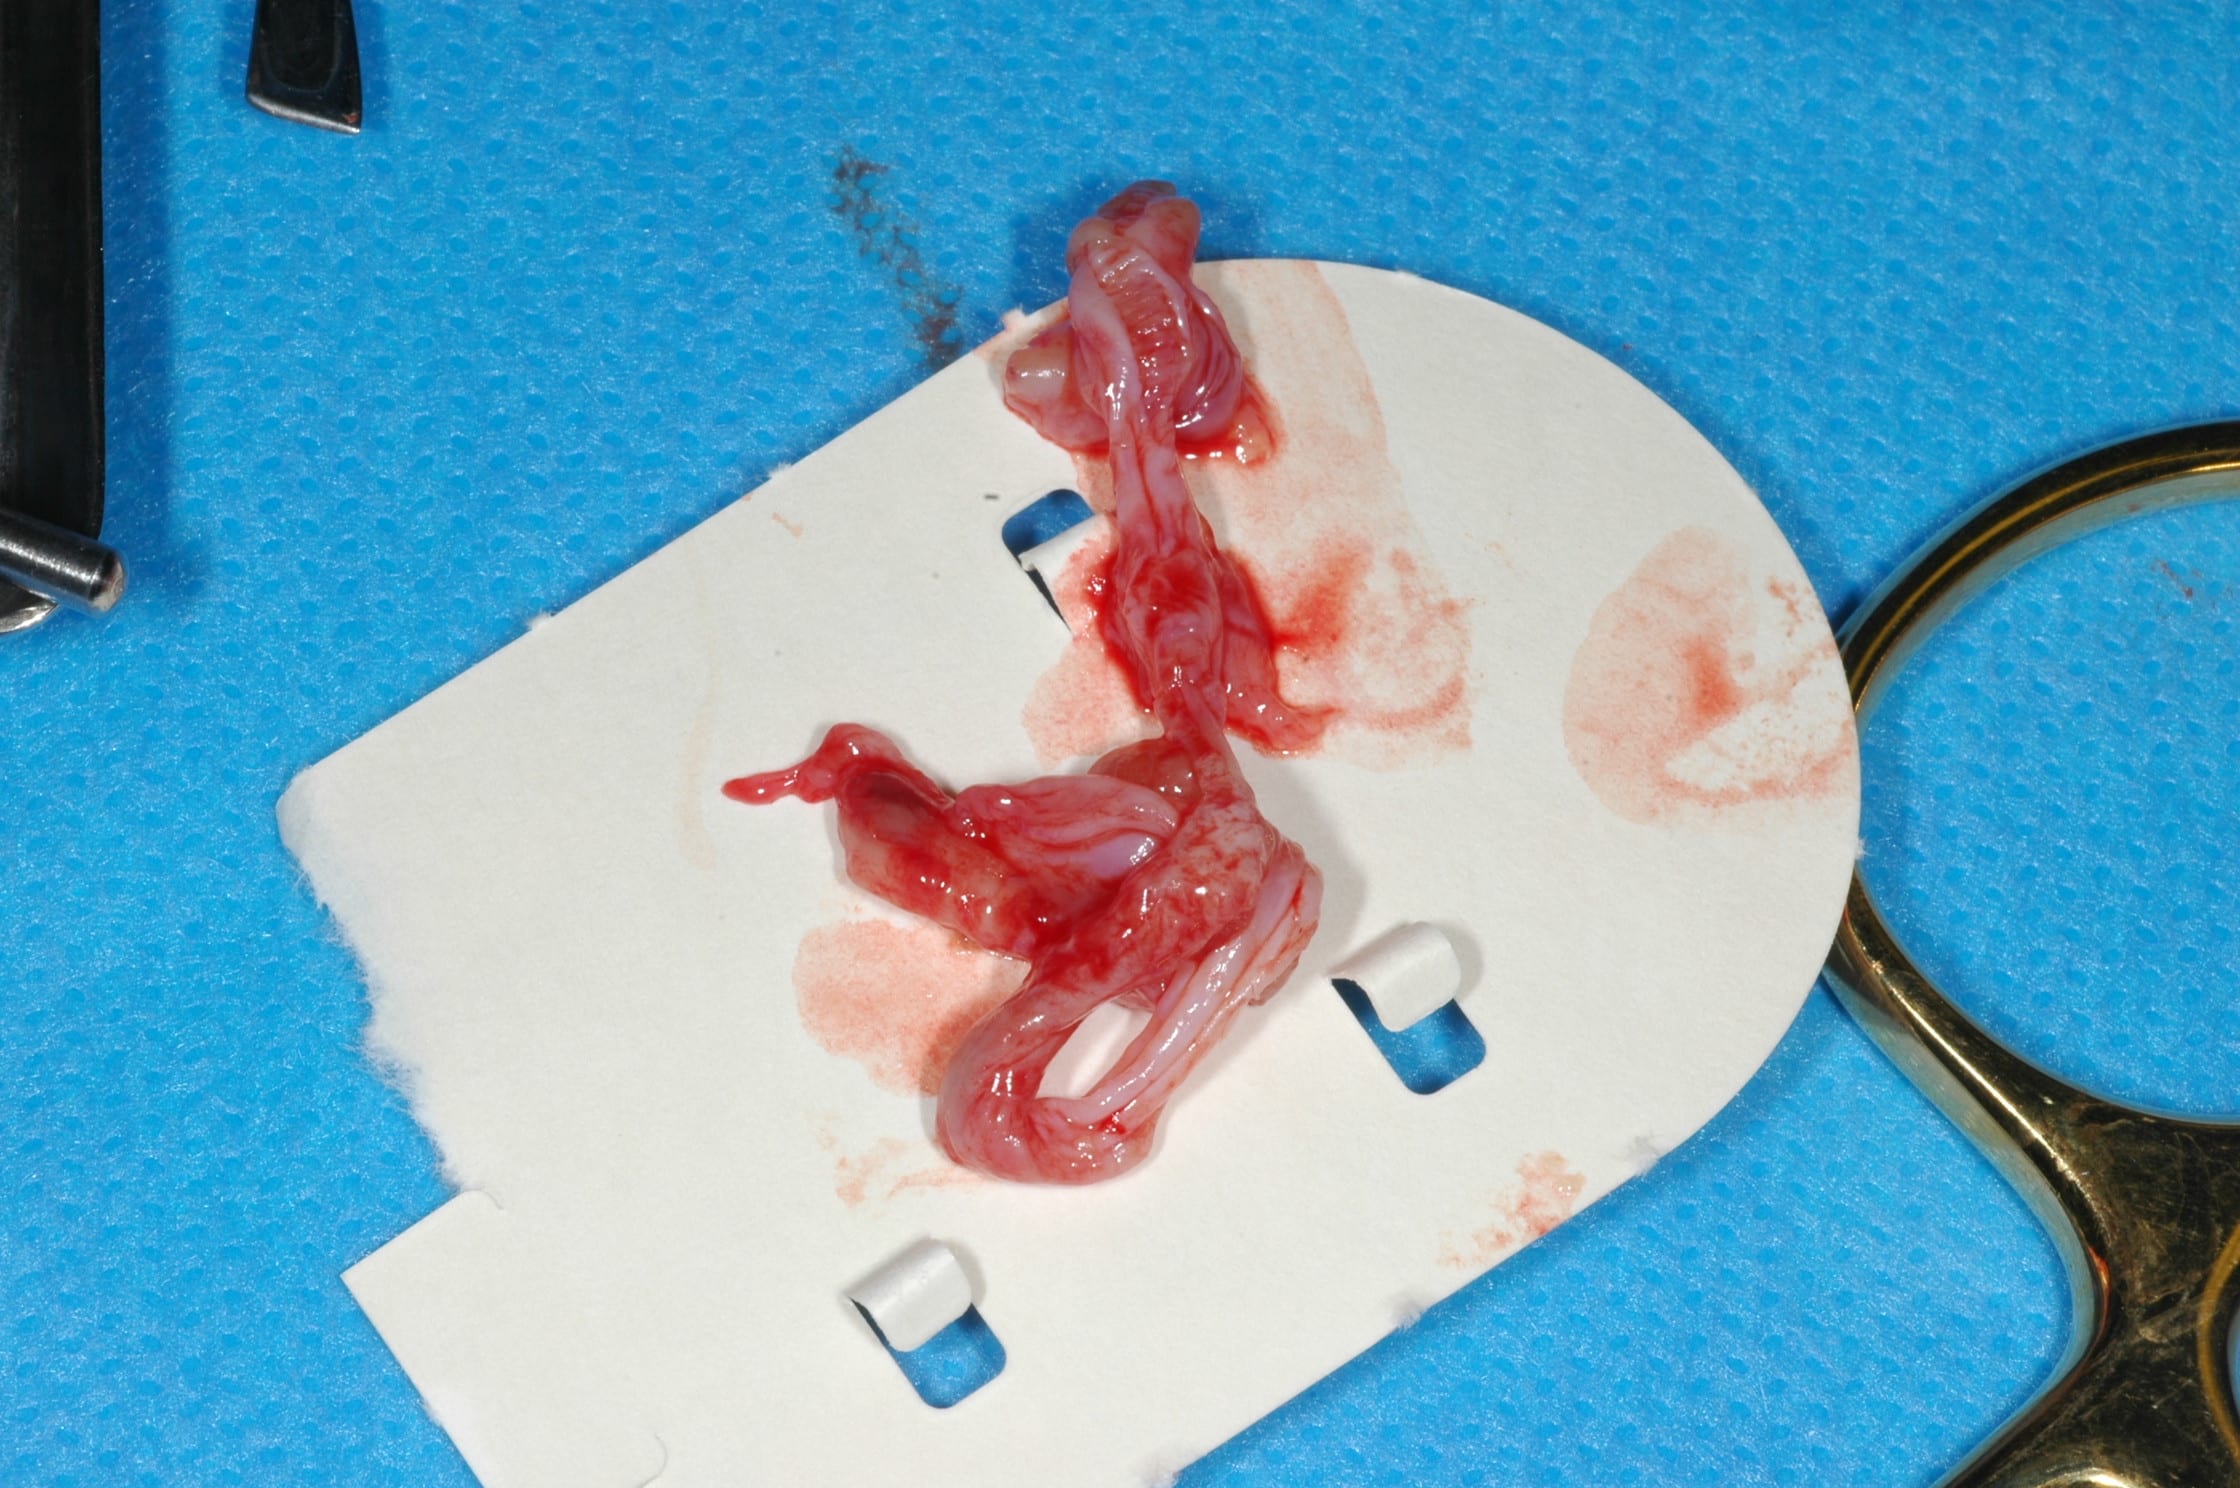

yeurk...c'est le placenta ou le cordon ombilcal ?

En continuant avec les envahissements de sinus.

Une idee de diagnostic? Evolution depuis 3 mois, facilement mobilisable, saignement a palpation, qui a envahit le sinus.

Patient a aucune douleur. Pas d adenopathies peripheriques.

En bonus un autre probleme de sinus...